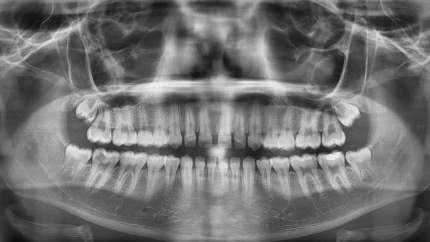

Radiografía panorámica dental | UNIOVI

El modelo destaca por su robustez, al haber sido entrenado con más de 10.700 ortopantomografías de jóvenes de entre 14 y 26 años. Las muestras proceden de doce países de cuatro continentes, lo que garantiza que la IA funcione con una diversidad real y justa. El sistema logra un error medio de apenas 1,12 años y, en la determinación del umbral legal de los 18 años, alcanza una precisión del 88,38%.